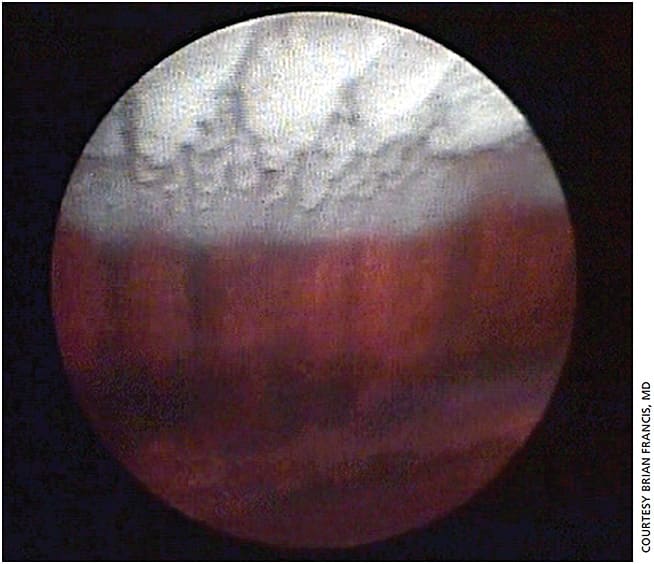

ECP can be useful in other types of glaucoma, Dr. Francis adds. For example, patients with plateau iris syndrome are refractory to iridotomy and iridoplasty and in some cases, lens removal. These patients can benefit from endoscopic cycloplasty (ECPL) and lens extraction.5 “We take out the lens but use the laser to treat and shrink the ciliary processes in the eye,” Dr. Francis says. “The pathogenesis of plateau iris is very large; anteriorly rotated ciliary processes push the iris forward and close the angle. By directly viewing and shrinking those processes, you’re pulling them away posteriorly from the iris, thereby opening up the angle (Figure 2). We have found that to be more effective in these severe patients than just taking out the lens.”